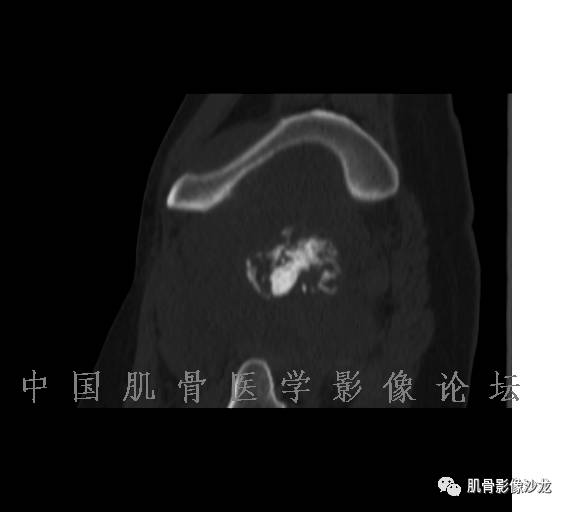

雪舞 :第二例,位于骶骨,有骨质破坏并有软组织肿块,软组织肿块边界清

雪舞: 第二例我们能够看到破坏与软组织肿块不成比例,软组织肿块大,破坏小

雪舞 :第二例挺难的,骨质破坏是溶骨性的,局部皮质中断,软组织肿块外缘光滑

雪舞 : 软骨肉瘤的发病率居原发性恶性骨肿瘤的第三位,其特点是肿瘤内具有软骨基质

雪舞:弓形钙化,钙化比例少于面积的1/3,钙化边缘模糊

雪舞 : 都是软骨肉瘤鉴别于内生软骨瘤有意义的区别点